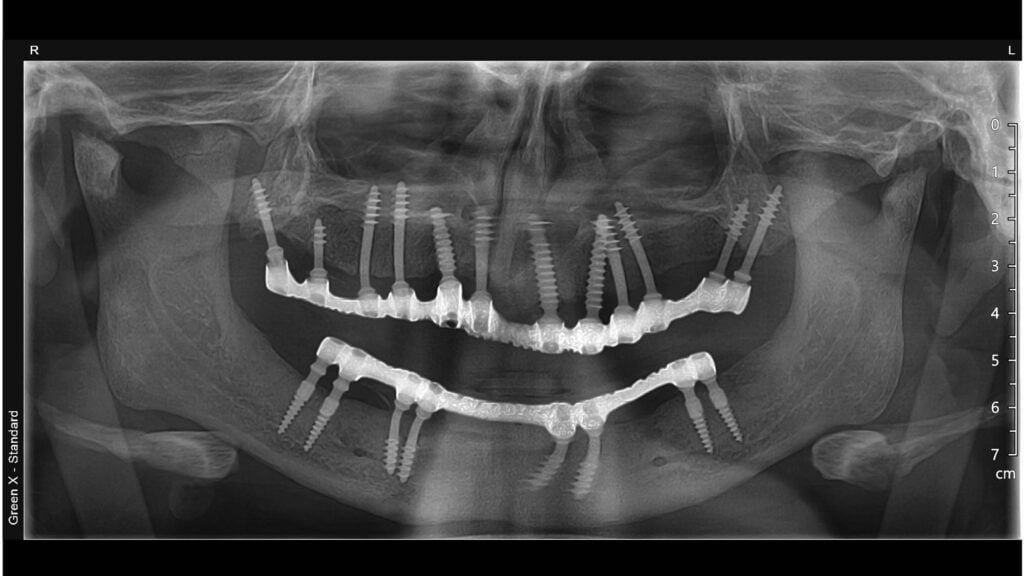

Rickets is a condition characterized by severe calcium insufficiency and low bone integrity, which poses substantial hurdles to dental rehabilitation. Patients with rickets frequently experience early tooth loss and skeletal malformations, which impair their ability to walk and stand normally. The Best Implantologist in Delhi NCR – Dr. Vivek Gaur, successfully handled one such patient. This case study looks at a ten-year follow-up on a patient with severe calcium shortage who had a complete mouth rehabilitation with Corticobasal® implantology while adhering to an immediate functional loading protocol.

➔Pre-Surgical Assessment: A thorough examination of bone quality and general health. It involved blood testing, X-rays, and 3D imaging to map the jaw anatomy.

➔Surgical Phase: Corticobasal® implants are placed after an immediate functional loading protocol. These implants are made to anchor in the basal bone, which is unaffected by rickets-related problems withv Regardless of the bone quality.

During the 10-year follow-up, the patient showed impressive improvement:

★Implant Success: All implants remained stable, showing no evidence of rejection or failure.